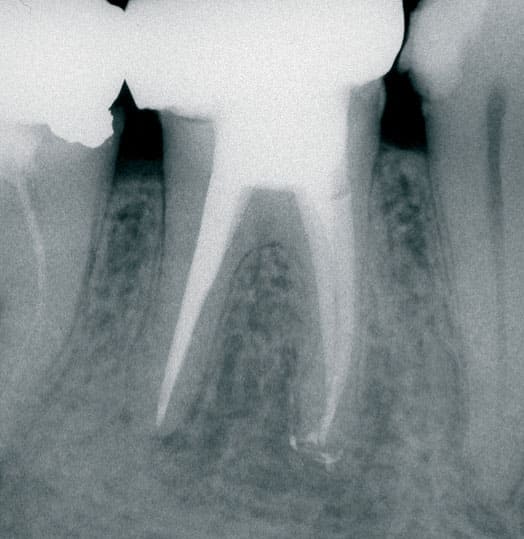

La chirurgie endodontique regroupe l’ensemble des interventions destinées à traiter l’intérieur de la dent lorsque les traitements classiques ne suffisent pas. Elle permet de conserver des dents fragilisées ou présentant des anatomies complexes, en intervenant directement au niveau des racines et des tissus environnants. Réalisée sous anesthésie locale et avec des techniques microchirurgicales modernes, elle constitue une alternative efficace à l’extraction dentaire.

La chirurgie endodontique est indiquée dans les cas où un traitement ou un retraitement du canal radiculaire ne peut pas être réalisé avec succès. Cela peut concerner des dents dont les canaux sont obstrués, fracturés, difficilement accessibles, ou encore en cas d’infections persistantes. Cette approche offre une chance supplémentaire de sauver la dent naturelle.

L’acte le plus courant en chirurgie endodontique est la résection apicale, qui consiste à retirer l’extrémité infectée de la racine. D’autres interventions peuvent également être pratiquées, comme l’exploration chirurgicale de canaux difficiles ou le retrait de matériel obstruant. Ces gestes, réalisés avec des instruments de précision et sous microscope opératoire, assurent un contrôle maximal et un résultat fiable.